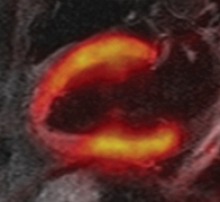

En un estudio publicado en la edición de mayo de 2013 de la revista Radiology se sugiere que es posible la obtención de estudios cardiacos PET/RM -en equipos híbridos de cuerpo entero- con suficiente calidad diagnóstica como para su permitir su uso clínico en pacientes con enfermedad cardiaca isquémica; pero esta modalidad híbrida debe aún probar su valor agregado y relevancia clínica.

El estudio, realizado en el hospital universitario de Essen en Alemania, encontró buena concordancia entre las imágenes de PET con F18-FDG y las imágenes de RM adquiridas simultáneamente, en lo que respecta a series cinemáticas y de reforzamiento tardío con gadolinio, en un grupo de pacientes con infarto de miocardio.

Los equipos híbridos PET/RM constituyen una promisoria herramienta para la evaluación de pacientes cardíacos, debido a la gran resolución espacial de la RM y la posibilidad de registrar con exactitud las imágenes moleculares del PET, sin la exposición radiante adicional que representa el CT.